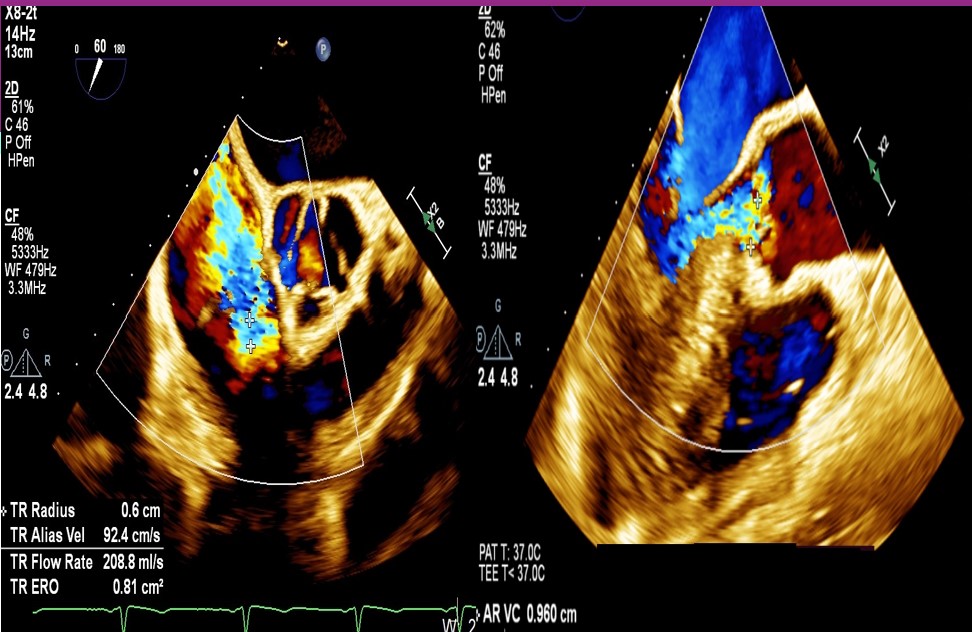

TTE was suggestive of valvular heart disease with severe AR, mild MR and severe TR with chordae rupture and prolapse of anterior leaflet of the tricuspid valve. TEE showed bi-atrial enlargement, left ventricular dilatation with diastolic dimension of 70mm. Left ventricular function was normal with ejection fraction of 70%. Aortic valve was thickened with no calcification of leaflets. Tricuspid annulus dimension measured 47mm, coaptation gap was 4.6mm with regurgitation volume of 65 ml.

First, through the right femoral vein, the Neoblazar® delivery system (Dawneo Neoblazar, Hangzhou, China) was advanced till the tricuspid valve, and two clips (TMrCLAMP-S) were deployed to grasp the anterior and septal leaflets with a desired outcome reducing to a mild residual TR. Postoperative VC width was 0.2cm with EROA of 0.17cm2 and regurgitation volume of 15mL. The delivery system removed and 18 fr sheath exchanged. A 5 fr temporary pacemaker wire positioned through sheath into the right ventricle. Subsequently, the right and left femoral arteries were each accessed with 6-fr sheath and 22 fr sheath respectively. Through the left femoral artery, the TAVI delivery system with a 30mm VitaFlow Liberty™ self-expanding valve system (MicroPort®, Shanghai, China) was advanced across the aortic valve and deployed under transoesophageal and fluoroscopic guidance with rapid ventricular pacing at 140 beats/minute and pacing slowly tapered. The mean valvular gradient after TAVI decreased to 6 mmHg. Then, percutaneous access closure of arterial access was achieved using a pre-closure technique with the suture-mediated ProGlide device (Abbott Laboratories Inc., Chicago, Illinois, United States). The total procedure time was 60min. There were no intraoperative complications. The temporary pacemaker was removed two days later. Predischarge transthoracic echocardiogram showed a normal functioning aortic THV with a mean gradient of 6mmHg and mild residual tricuspid regurgitation.